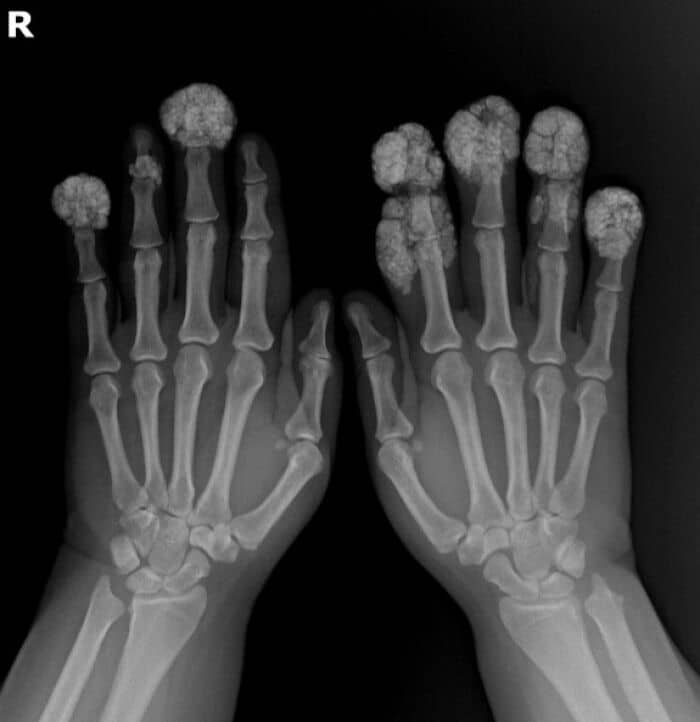

#15 X-Ray Of A Hand With Advanced Rheumatoid Arthiritis